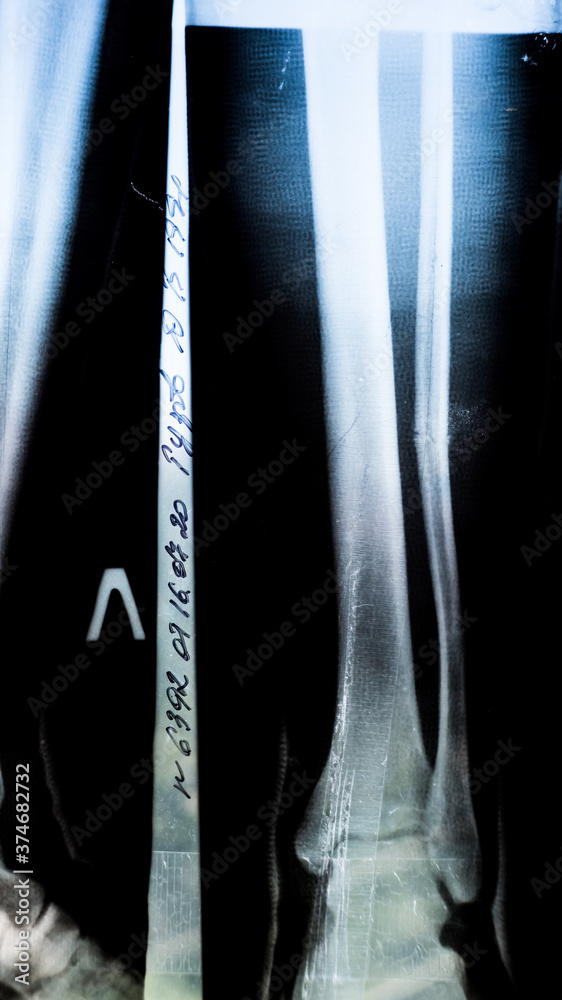

Xray of a patient with a fracture of the fibula of the middle tibia closeup in the hospital on X-Rays Of Broken Tibia Fibula Tibia or fibular fractures that involve the knee (e.g.,. Comminuted tibia fractures with fracture displacement. High force impact injury to the tibia and fibula. You’ll need at least one of a few imaging tests to take. what tests are done to diagnose tibia and fibula fractures? fractures of the tibia and fibula are usually easily spotted. computed. X-Rays Of Broken Tibia Fibula.